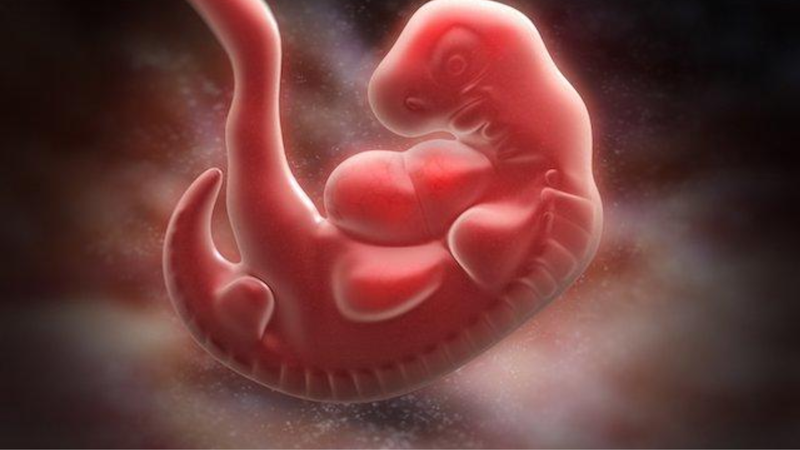

Bước sang tuần thứ 5, có nghĩa là bà bầu đã bước vào tháng thứ hai của thai kỳ. Hiện tại, túi thai có kích thước như một hạt tiêu và trông giống một chú nòng nọc. Thai nhi đã làm tổ trong tử cung và đang phát triển rất nhanh, có thể tăng gấp đôi kích thước chỉ sau một tuần.

Vậy cụ thể thì thai nhi lúc 5 tuần tuổi có những thay đổi gì? Dưới đây là một số phát triển của thai nhi khi đạt 5 tuần tuổi:

Não, tủy sống và hệ thống dây thần kinh của thai nhi phát triển từ một ống thần kinh duy nhất, được hình thành từ lớp tế bào ngoài cùng - ngoại bì. Bên cạnh đó, ngoại bì cũng phát triển thành da, tóc, móng, men răng, tuyến vú và tuyến mồ hôi.

Tim và hệ thống tuần hoàn khởi đầu phát triển từ lớp giữa - lớp trung bì. Vào tuần thai thứ 5, tim đã bắt đầu đập và bơm máu để nuôi dưỡng cơ thể. Ngoài ra, lớp trung bì còn tạo ra hệ cơ, xương, sụn và lớp mô dưới da của em bé.

Lớp tế bào bên trong cùng - nội bì - sẽ phân hóa và phát triển thành phổi, ruột, gan, tụy, cũng như hệ tiết niệu và tuyến giáp. Bên cạnh đó, tế bào nhau thai nguyên thủy và dây rốn cũng bắt đầu hình thành, chịu trách nhiệm vận chuyển oxy và dinh dưỡng từ mẹ sang thai nhi.